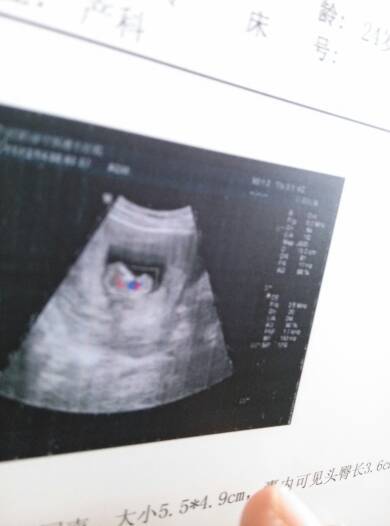

谁能告诉我!这B超能看到什么!还有那红色和蓝色是虾米 谁能告诉我!这B超能看到什么!还有那红色和蓝色是虾米 点击展开 大饼cy 2014-11-12 16:13 为您推荐: 其他回答 我也不会看 琼琼妈妈^ω^ 2014-11-22 20:49 正常没事的 年少的狂妄 2014-11-18 17:41 能看到胎宝宝啊 其他没什么的 祝好孕 138*****520_p0AS 2014-11-17 15:03 加微信lkalnn,看有适合宝妈妈得衣服吗 Lkalnn 2014-11-17 07:54 不客气的,有问题欢迎随着咨询。 唐海平主任 2014-11-13 16:10 加载更多 相关问题 B超上的蓝色的和红色一小块一小块的什么啊 我媳妇怀孕三个月了,昨天去医院检查,胎儿各项发育正常,想问B超上的红色和蓝色是什么意思? 去照B超问男女,问医生:我要买蓝色的衣服还是红色的衣服?她回答:不要买裙子就好了!可是后面又说小孩子的衣服不分颜色的 到底是什么意思?谁能告诉我呢?